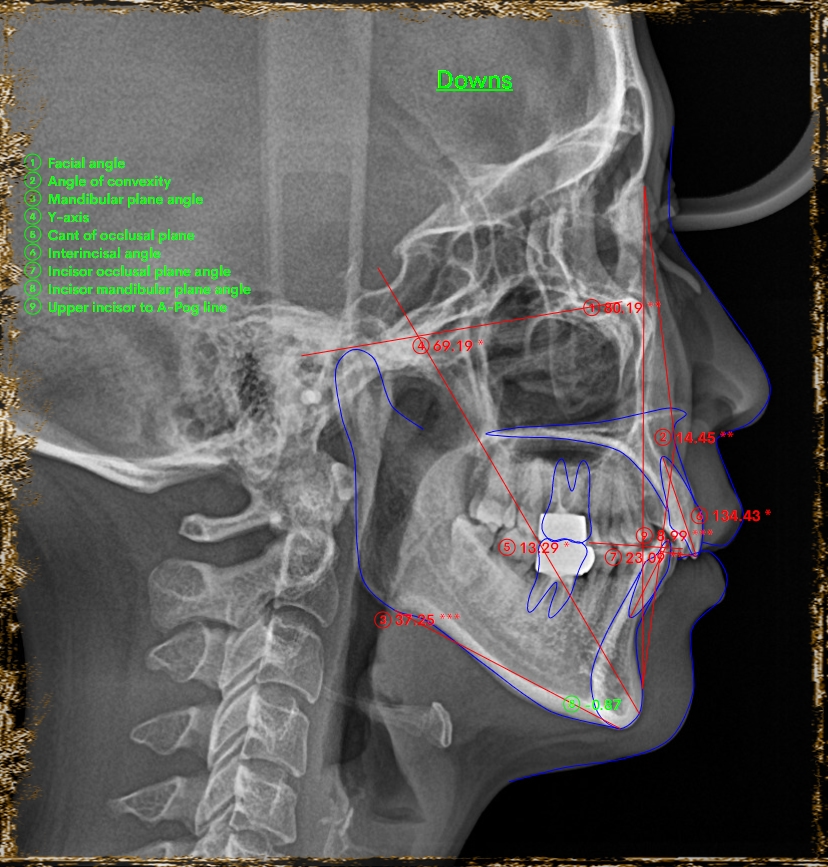

Một trường hợp điển hình của nhóm bệnh nhân hô hàm hô cả xương, lại có cả chen chúc răng. BN thiếu R31 bẩm sinh, sai khớp cắn hạng II chi 2 có chen chúc hàm trên như này thì rất dễ bị khớp cắn sâu nếu nhổ răng đều. Sau phân tích và tính toán thì BN được chỉ định nhổ 3 răng số 4 để kéo giảm hô.

Kết quả: sau 1.5 năm điều trị, BN được tháo niềng